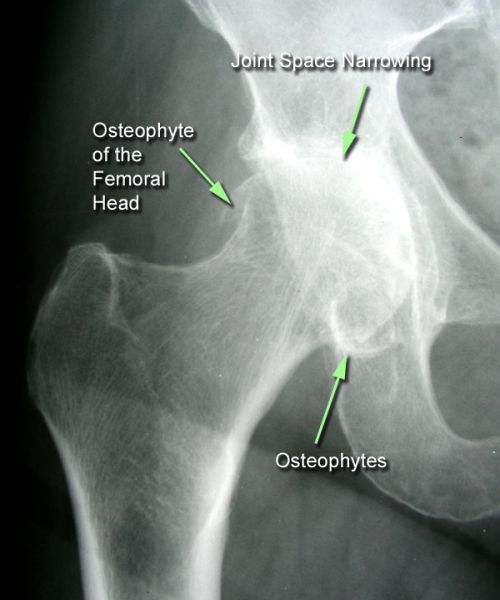

Αποτελεί μια εκφυλιστικού τύπου αρθρίτιδα της άρθρωσης του ισχίου. Με την πάροδο του χρόνου προκαλείται παραμόρφωση της αρθρικής επιφάνειας τόσο στην κεφαλή του μηριαίου όσο και στην κοτύλη.

Εμφανίζεται συχνότερα σε γυναίκες προχωρημένης ηλικίας ενώ υπάρχει και γενετικό υπόβαθρο προδιάθεσης. Παρουσιάζει αυξημένη συχνότητα εμφάνισης σε ασθενείς με συγγενή δυσπλασία ισχίου, ιστορικό αγγειακού τραυματισμού της κεφαλής του μηριαίου, επαγγελματίες αθλητές καθώς και σε άτομα με επαγγέλματα που σχετίζονται με άρση βάρους και έντονη μυϊκή καταπόνηση.

Η κλινική εξέταση αναδεικνύει άλγος στην περιοχή του ισχίου κατά τις κινήσεις της άρθρωσης, χωλότητα βάδισης λόγω άλγους, μείωση της έκτασης - κάμψης και έσω στροφής του ισχίου. Η επιβεβαίωση της διάγνωσης γίνεται με απλή ακτινογραφία.

Η θεραπεία είναι η χρήση φαρμακευτικής αγωγής, χρήση βοηθημάτων βάδισης (μπαστούνι), απώλεια βάρους καθώς και φυσικοθεραπείες.

Σε προχωρημένη αρθρίτιδα ασθενούς άνω των >50 ετών όπου πλέον ο ασθενής εμφανίζει νυχτερινό άλγος και δυσκολία στις απλές καθημερινές κινήσεις η σύσταση είναι για χειρουργική αντιμετώπιση με ολική αρθροπλαστική ισχίου. Το χειρουργείο γίνεται με τις πιο σύγχρονες , ελάχιστα επεμβατικές μεθόδους και ο ασθενής περπατάει την ίδια μέρα, χωρίς πόνο, με ελάχιστη νοσηλεία και με άμεση επάνοδο στις καθημερινές του συνήθειες.